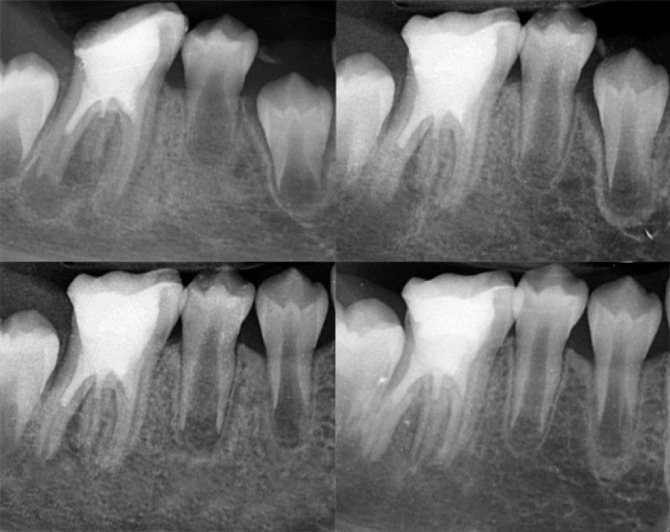

Regenerative endodontic procedures (REPs) have emerged as a biologically driven approach for managing immature teeth with necrotic pulp and open apices, providing an alternative to traditional apexification techniques. This case report describes the successful treatment of a three-rooted immature mandibular first molar with necrotic pulp and chronic apical periodontitis in a 9-year-old patient using REPs. The treatment followed the guidelines set by the American Association of Endodontists and utilized a two-visit protocol. Concentrated growth factor (CGF) was employed as a biological scaffold in the root canals, while calcium-enriched mixture (CEM) cement was used for the coronal seal. Radiographic evaluations conducted at 6, 12, and 15 months revealed progressive periapical healing, significant root elongation, increased thickness of the root walls, and partial apical closure. Clinically, the patient remained asymptomatic during all follow-ups. This case highlights the potential of CGF and CEM cement-enhanced REPs to promote continued root development and achieve predictable outcomes in immature teeth with necrotic pulps, offering a biologically based alternative to conventional apexification.